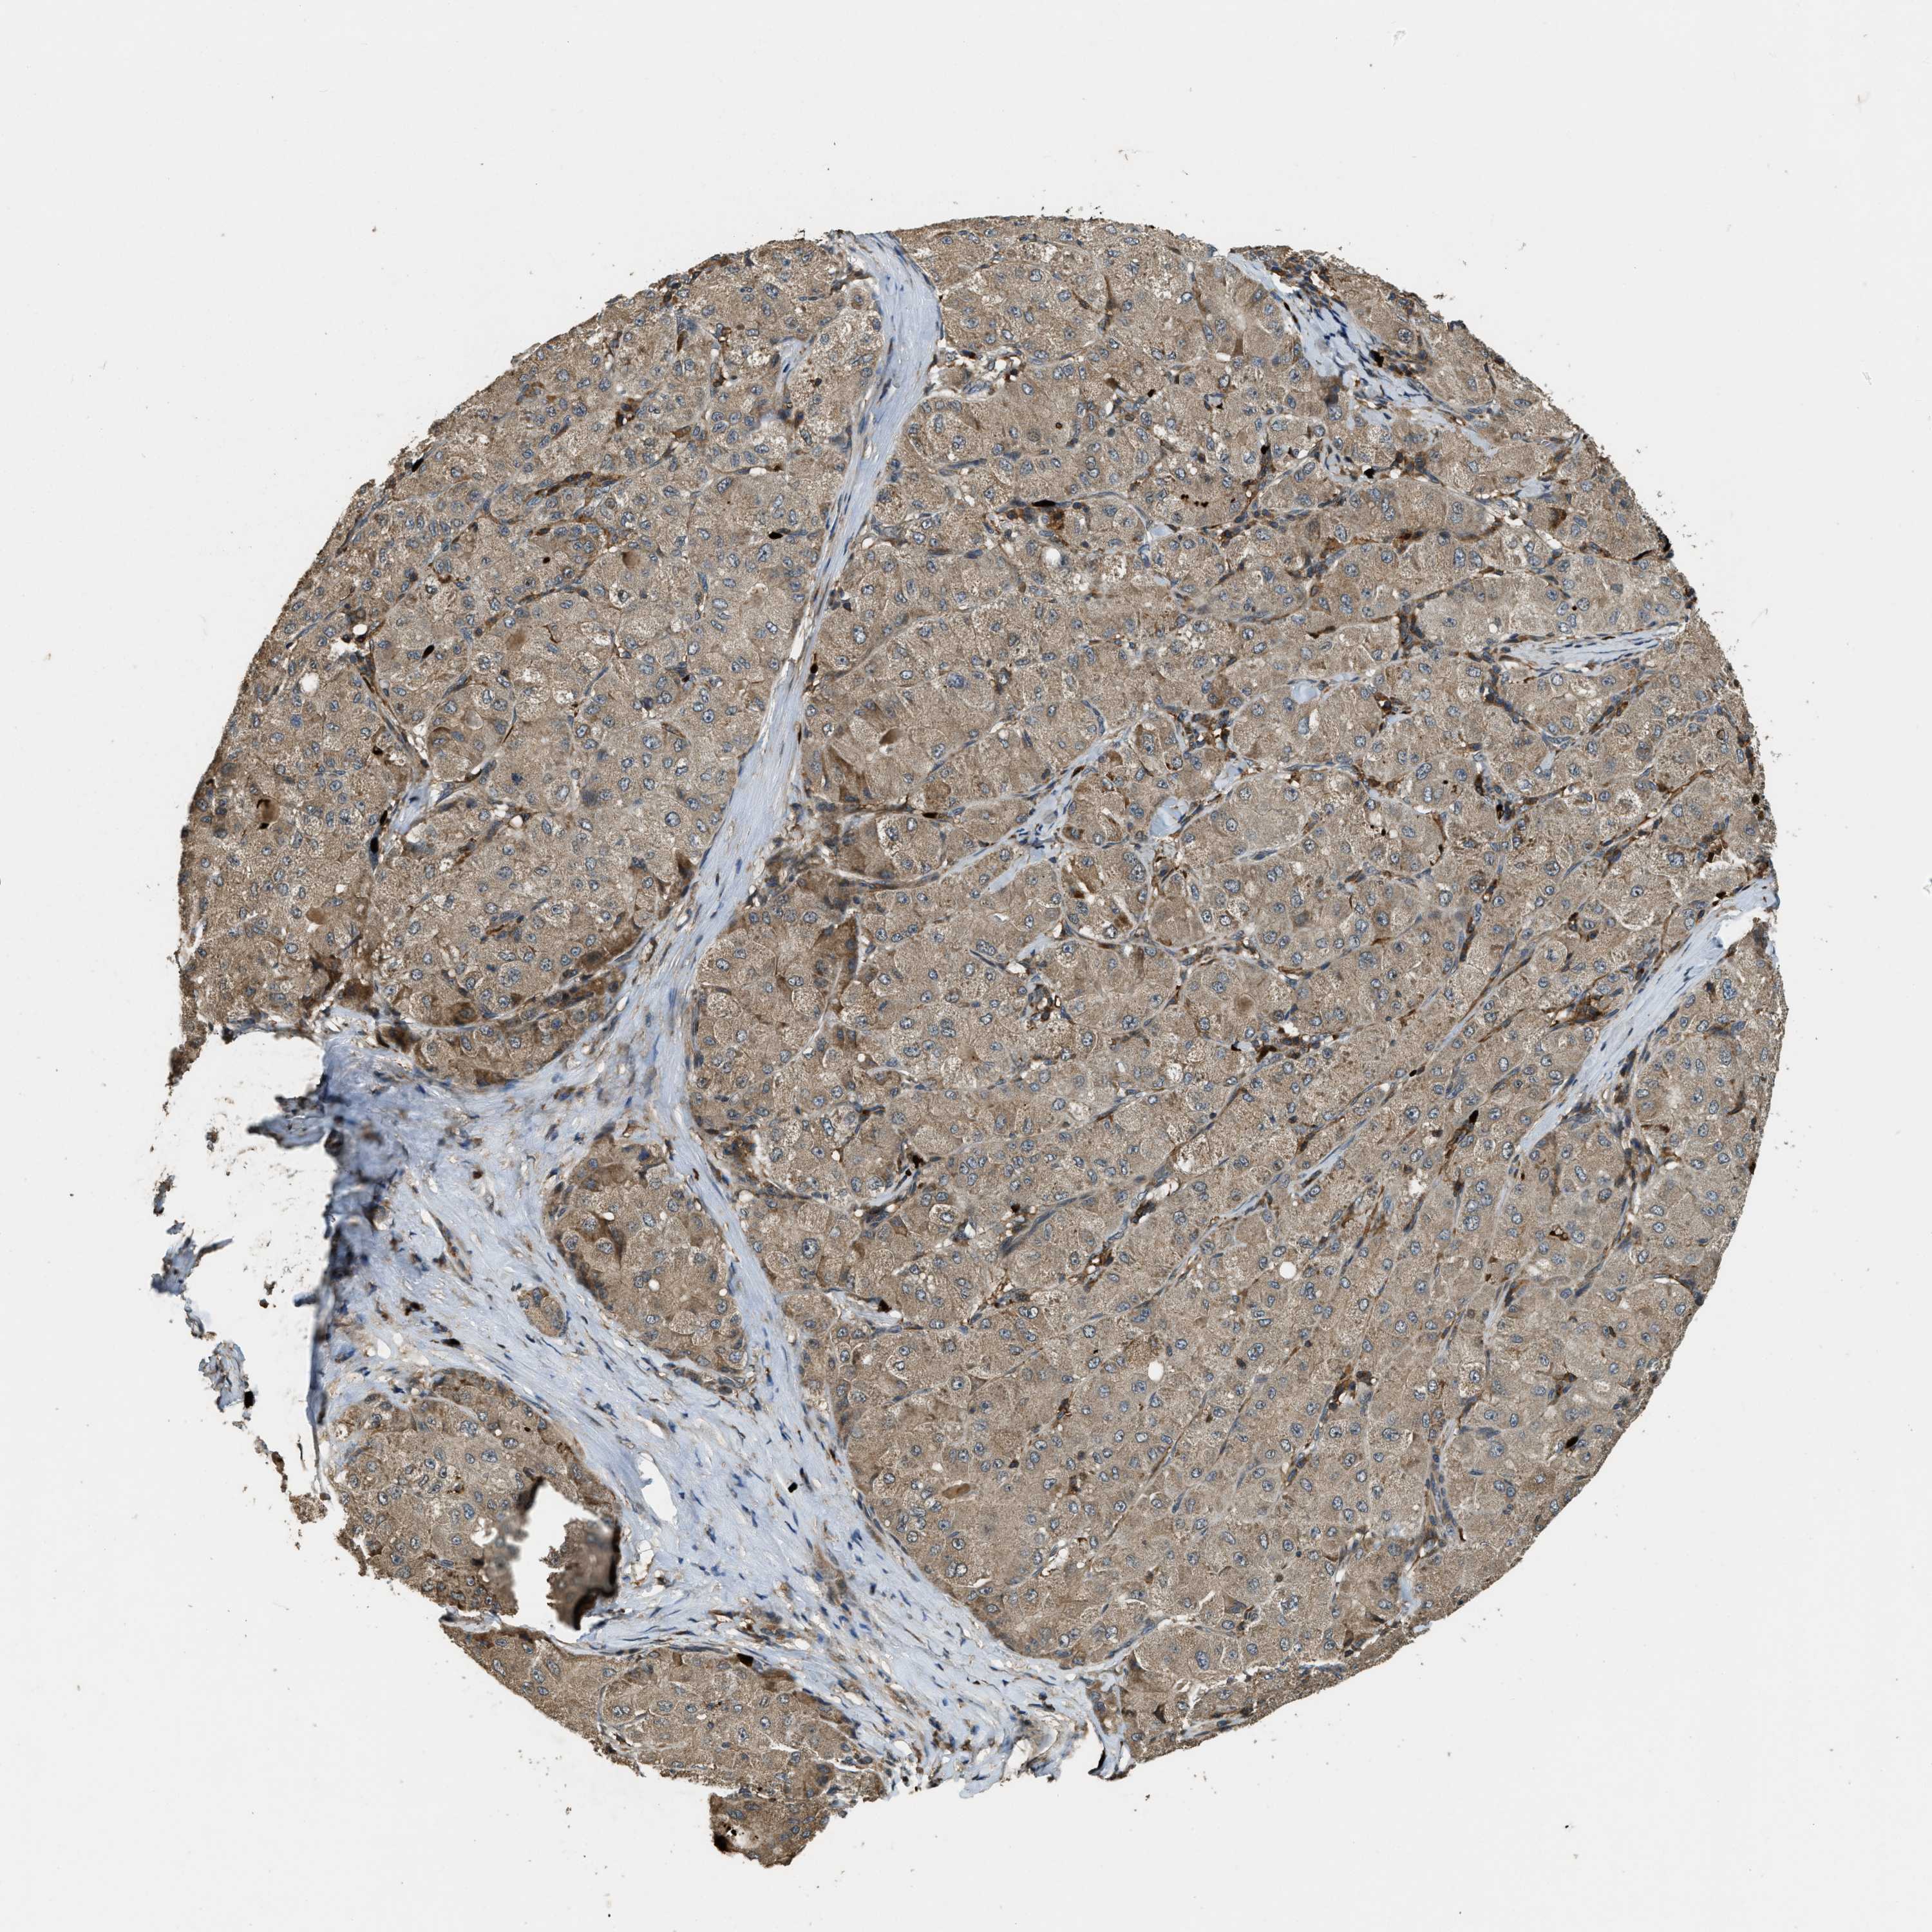

LIVER CANCER - Protein expressioni

A mouse-over function shows sample information and annotation data. Click on an image to view it in a full screen mode. Samples can be filtered based on level of antibody staining by selecting one or several of the following categories: high, medium, low and not detected. The assay and annotation is described here.

Note that samples used for immunohistochemistry by the Human Protein Atlas do not correspond to samples in the TCGA dataset.

Antibody stainingi

Antibody staining in the annotated cell types in the current human tissue is reported as not detected, low, medium, or high, based on conventional immunohistochemistry profiling in selected tissues. This score is based on the combination of the staining intensity and fraction of stained cells.

Each image is clickable and will lead to virtual microscopy that enables deeper exploration of all samples and also displays staining intensity scores, fraction scores and subcellular localization as well as patient and tissue information for each sample.

Antibody HPA018133

Staining

High

Medium

Low

Not detected

Intensity

Strong

Moderate

Weak

Negative

Quantity

>75%

75%-25%

<25%

None

Location

Nuclear

Cytoplasmic/membranous

Cytoplasmic/membranous,nuclear

Cholangiocarcinoma

Carcinoma, Hepatocellular, NOS